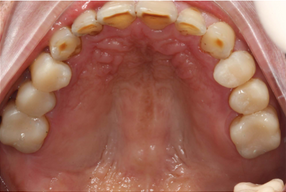

Mr NK, a 52-year-old male, presented with concerns of gradually shortening teeth and sensitivity to cold drinks. He also reported feeling self-conscious about his smile in photos. He is medically fit and has been using a night guard for his sleep-related grinding habit for the past year. Clinical examination revealed moderately worn dentition from erosion and attrition, along with mild crowding of the lower anterior incisors.

Intra-Oral Pictures (Before)

- Erosion severity: ACE Class Class III

- Reduced occlusal vertical dimension

- Mild crowding of lower anterior teeth